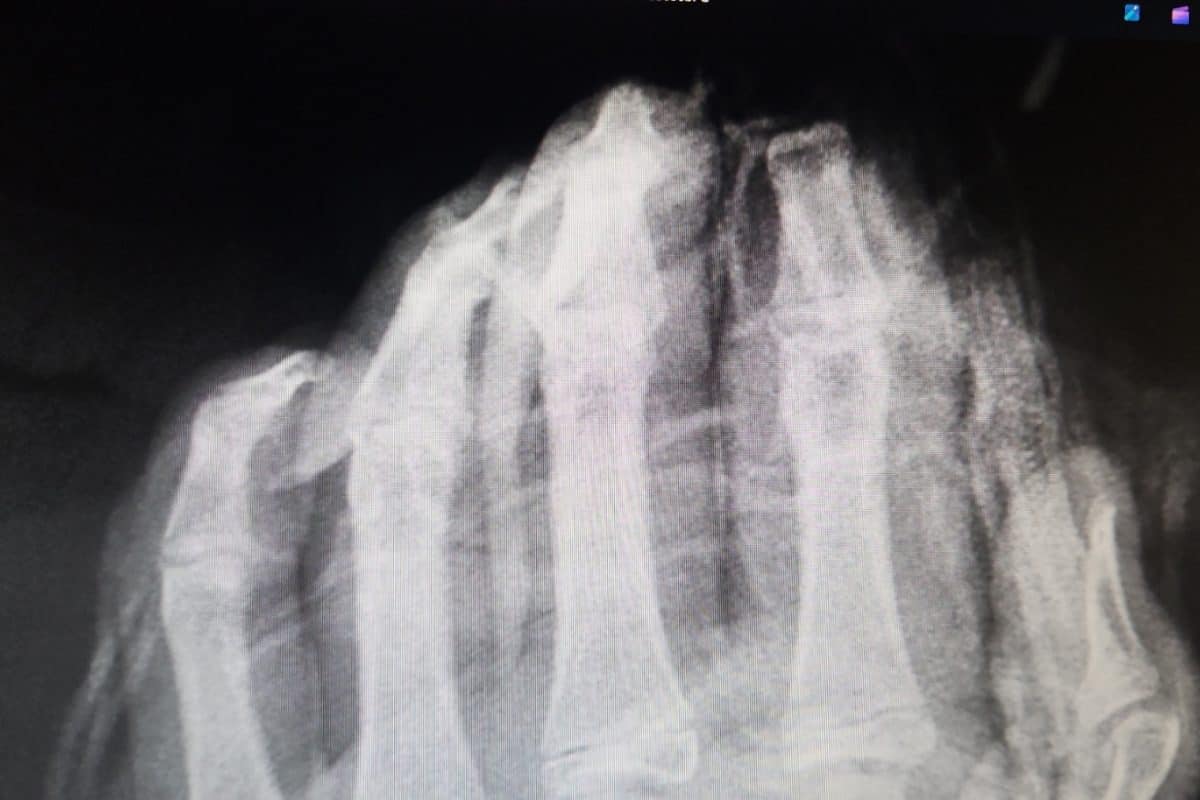

Andrej Strahovnik, dr. med., specialist kirurg iz Splošne bolnišnice Celje je spregovoril o nesrečah povzročenih s pirotehničnimi sredstvi. Povedal je , da so v tretjini vseh primerov poškodovane roke, sledi obraz, obrazni del ter poškodbe sluha in vida. V večini primerov gre za trajne posledice, saj eksplozija povzroči raztrganine, zmečkanine mikroembolije drobnih žil, poškodbe živcev in obsežne poškodbe mehkih tkiv, zato je potreben pri oskrbi tovrstnih poškodb multidisciplinaren pristop različnih vrst specialnosti. Poudaril je, da tudi najboljša kirurška tehnika včasih ne zmore popravit vsega, kar naredi drobec sekunde pri raztrganinah. Posebej zahtevna je tudi rehabilitacija. Največ poškodovancev je starih od 20 do 30 let, sledijo najstnik. Kar v 80 % gre za poškodovance v delovni dobi, kar jim precej spremeni ekonomski status. Povedal je še, da gre za poškodbe, ki jih je možno preprečiti z neuporabo in ne nakupom pirotehnike.

Ranko Lazarevič, 20 letni fant s Koroške, se je novembra lani hudo poškodoval pri uporabi pirotehnike. Pirotehnično sredstvo, za katerega je kasneje izvedel, da ni bilo kupljeno v trgovini, ampak izdelano doma, mu je odtrgalo desno roko, od zapestja. Ranko, ki je bil desničar se je po poškodbi začel učiti hranjenja, pisanja, oblačenja z levo roko. Na srečo je velik borec in optimist. Veseli se proteze, ki bi jo naj dobil še letos in zelo se veseli, da se bo s pomočjo proteze, čez nekaj časa znova vrnil v službo. Pok pirotehnike ga še vedno močno pretrese in misli odnese v trenutke groze. Vsem mladim polaga na srce, naj ne uporabljajo pirotehnike.